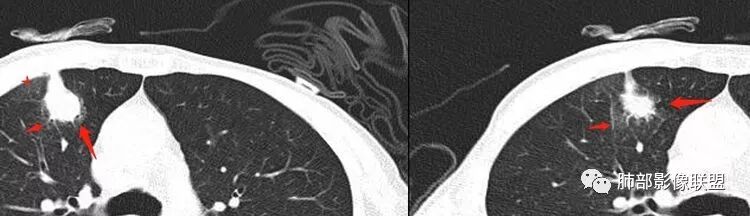

1.胸膜下不规则结节影,密度不甚均匀,有浅分叶、长毛刺,周边有磨玻璃晕。

2.有胸膜牵拉,尽管收缩能力不强。支气管相关(有细小支气管止于病灶内侧),加之病灶孤立、边界不清带晕,这些都不是血道转移病灶的特点。

左锁骨上及纵隔未见肿大淋巴结,注意这是胃癌的淋巴转移路径。